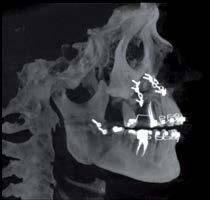

L’innovazione e la sicurezza sono due dei valori perseguiti dallo Studio Braconi a Terni, un punto di riferimento nell’ambito della radiologia 3D ortopedica grazie alla presenza del macchinario Newton 5G XL: si tratta dell’unico apparecchio nel Centro Italia che permette di eseguire una perfetta diagnostica per immagini in ortopedia e per la cervicale, oltre per le piccole articolazioni come seni paranasali, orecchie, colonna cervicale, gomito, polso, mano, ginocchio, caviglia e piede.

Nell’ambito della radiologia 3D ortopedica, il centro diagnostico utilizza il nuovissimo macchinario NewTom 5G XL, in grado di individuare con la massima precisione la presenza di fratture o lussazioni delle articolazioni, controllare la corretta guarigione di una frattura, valutare una lesione o una ferita causata da infezione, artrite o crescita anormale dell’osso.

Se con la radiologia tradizionale era necessario eseguire scansioni multiple, la novità introdotta dal macchinario NewTom 5G XL risiede nella capacità di fornire immagini ad alta risoluzione in un’unica scansione, mostrando nitidamente i dettagli delle articolazioni degli arti superiori e inferiori. Inoltre, a differenza della tecnologia 2D, la radiologia 3D ortopedica permette di individuare immediatamente alcune patologie come quella del metatarso, la quale richiede un allineamento visivo dedicato o una diagnosi delle micro fratture ossee.